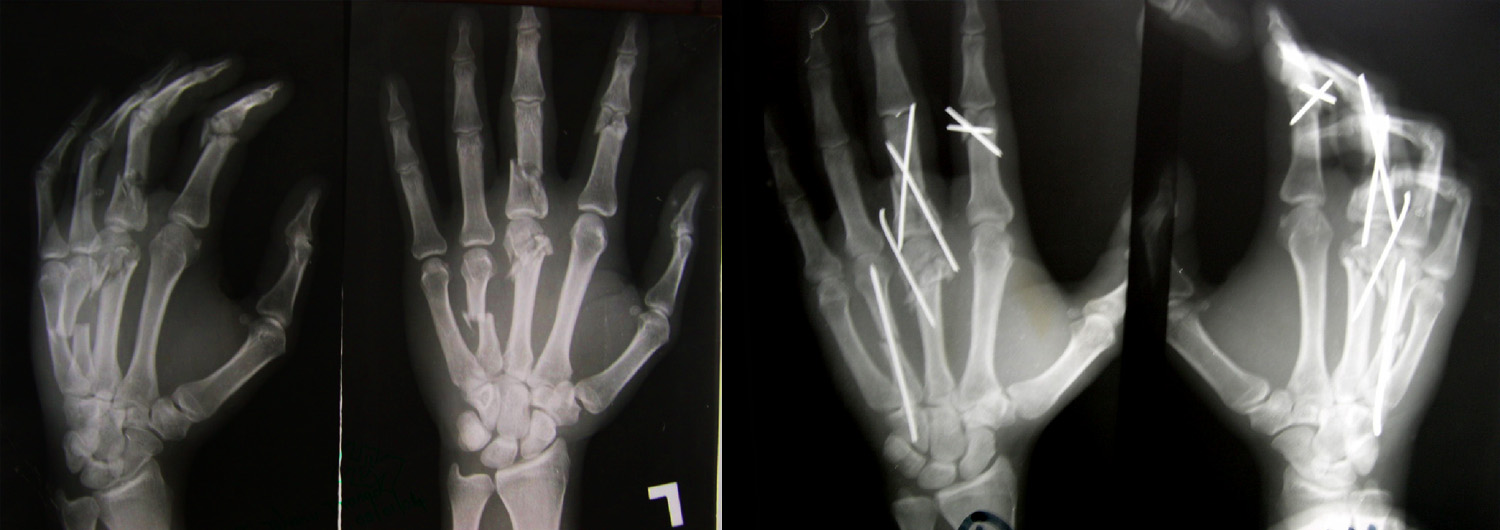

Fractures, to both hand and wrist, are caused by an impact to the bone that is strong enough to break it. Symptoms include severe pain, loss of movement and swelling. Whatever caused the fracture – whether it was a fall, a fight, a sporting accident or anything else – can influence the treatment, so it"s helpful for the surgeon to know exactly how the break occurred. The problem will most likely be dealt with first by an Accident & Emergency department, before being passed on to a hand surgery team, including the surgeon, nurses and therapists.

A surgeon will take x-rays and physically examine the fracture before deciding on the best course of action. In some cases, the fracture may be treated with a splint, hand exercises and painkillers, but more serious breaks may require an operation. Following surgery, it"s likely the fracture will be placed in a splint or plaster, and rehabilitation will be overseen by therapists, who will advise on exercises to help future movement in the affected area.